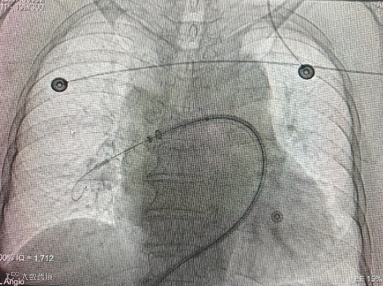

常规消毒铺巾,局麻后穿刺右股静脉成功后,置入血管鞘,行肺动脉造影术,提示右肺动脉上叶支主干栓塞。

术前造影